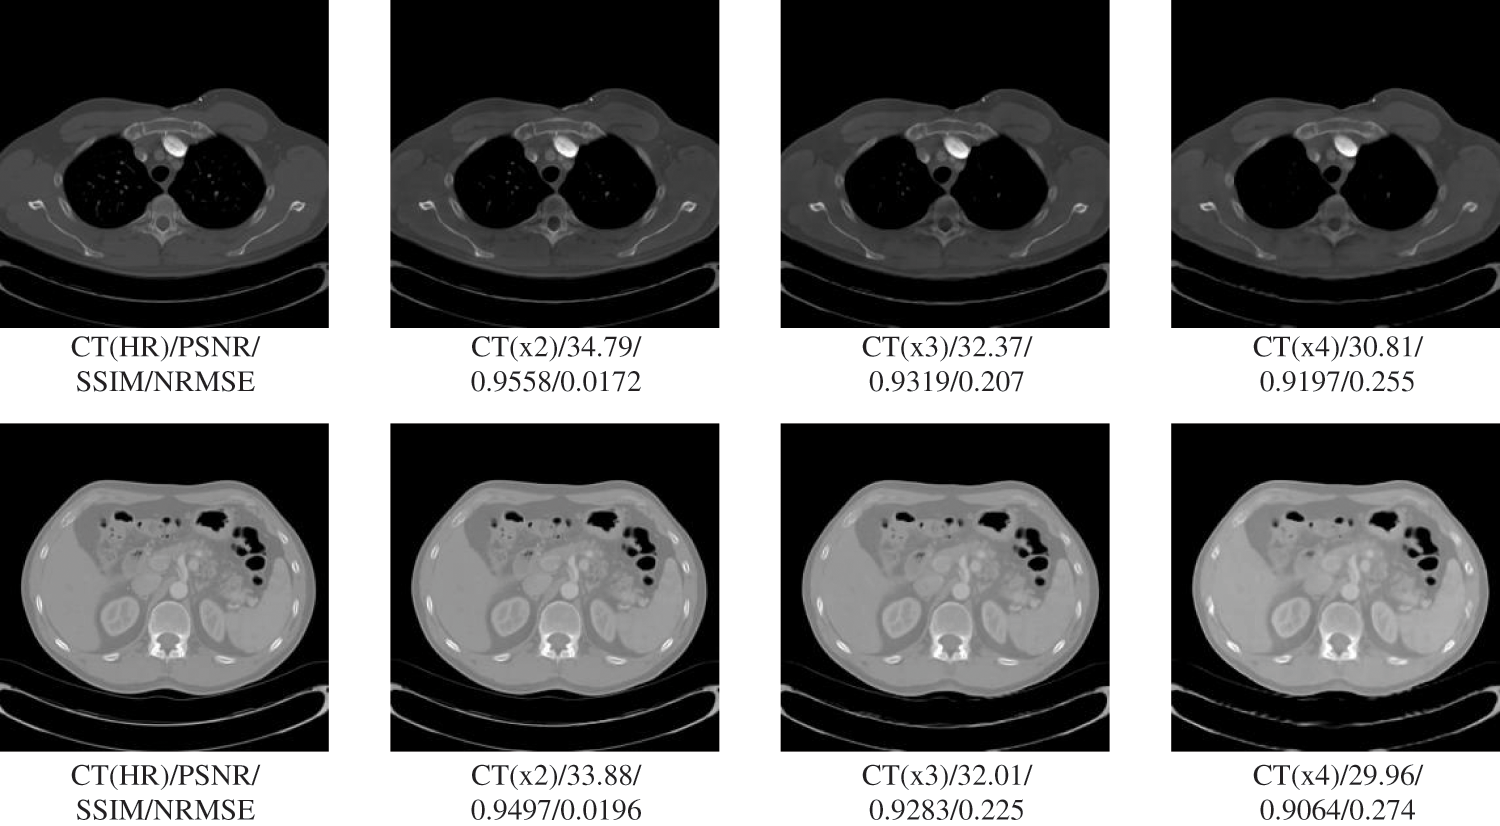

In this section of experiments, we focus on testing the processing effect and network performance of the proposed multi-scale super-resolution network. This section does not involve the comparative study with other publicly available models and the generalizability test of the proposed network in different parts. Therefore, this section mainly uses a single CT dataset of pelvic sites for testing, with three test patient samples and 200 test slices. This section evaluates the super-resolution performance at different scales, using three evaluation metrics with pixel-level visualization difference maps in terms of both numerical and visualization effects, respectively. The visualization effect of super-resolution processing at different scales is shown in Fig. 3.

Figure 3: Results of pCT 6-scale SR images of the pelvis

Table 1 shows the performance of the six scales of SR processing results under three evaluation metrics tested at 200 slices. The table reflects the general trend that the larger the scale, the lower the quality of the super-resolution processing results. However, based on the general analysis of the above graphs, it can be seen that, concerning the results obtained so far, the single-model multi-scale super-resolution processing network has undoubtedly met the requirements for image augmentation and guaranteed image quality. Even the 4x SR processing with the lowest performance can still guarantee a PSNR of about 33 and an SSIM index above 0.95, which has met the requirements of multiple processing methods for image quality. For example, alignment, segmentation, fusion, diagnosis, etc. This shows that our proposed network has an excellent application on a single source with a single site.

The results in Table 3 show that our proposed SR algorithm is superior in terms of generalization to different parts compared to the two deep learning SR methods. The test sample used in the lung visualization results in Fig. 4 is a 512 × 512 slice, while the liver test sample in Fig. 5 is a 160 × 192 slice. Comparing the SR results of the two figures shows that the SR processing results are better at high magnification when the LR image contains more information. Although the 4x SR results are not ideal in the liver, the quality of the results of 2x SR is sufficient for use. Therefore, it can be verified that the generalizability of our proposed method to different sites is also excellent.